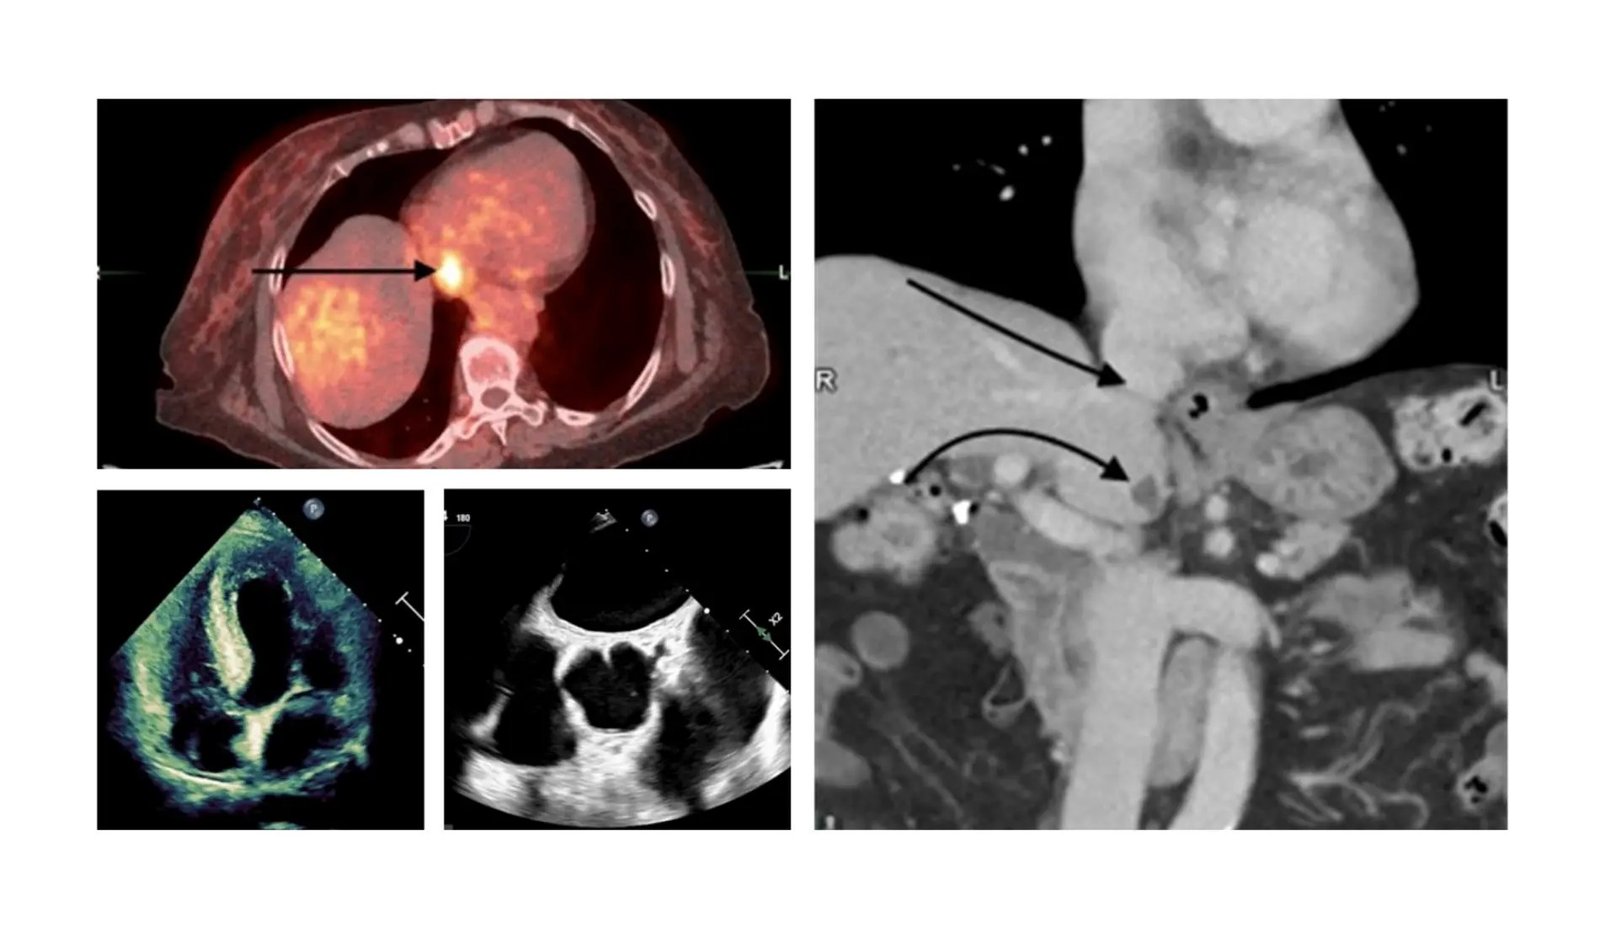

Busra Cangut detalha: “Um exame PET/CT com 18F-FDG (uma glicose radioativa) realizado para determinar o estadiamento do câncer mostrou intensa atividade no átrio direito, semelhante a uma hérnia de tecido mole. Um exame mais profundo subsequente usando ecocardiografia transesofágica (ETE) confirmou conclusivamente que o que foi visto foi na verdade uma hérnia de crista terminal, uma variação comum na anatomia cardíaca”. diagnosticada com câncer de mama. Sua PET/CT 18F-FDG, parte de sua avaliação de câncer, mostrou inesperadamente atividade significativa em seu átrio direito, inicialmente indicando uma massa potencialmente perigosa. Esta observação preocupante levou a uma avaliação mais aprofundada, que foi esclarecida como uma crista terminal proeminente, uma variação típica da estrutura cardíaca.

“A crista terminal está localizada no átrio direito e corre ao longo da parede lateral entre as duas veias principais (veia cava superior e inferior). Em alguns casos, a atividade normal do F-18 FDG na crista terminal pode ser erroneamente identificada como um trombo tumoral, como aconteceu no nosso caso. Portanto, ao analisar essas imagens, é crucial ter uma compreensão profunda da captação normal e de suas alterações nas estruturas cardíacas padrão”, enfatizou o Dr. Este estudo é importante para demonstrar os desafios de interpretar com precisão essas imagens. A crista terminal pode apresentar atividade que pode ser confundida com sinais de trombo tumoral, o que é uma preocupação em pacientes com câncer. Este estudo destaca a importância de uma compreensão completa da captação fisiológica normal e das alterações benignas nas estruturas cardíacas padrão para evitar interpretações errôneas.